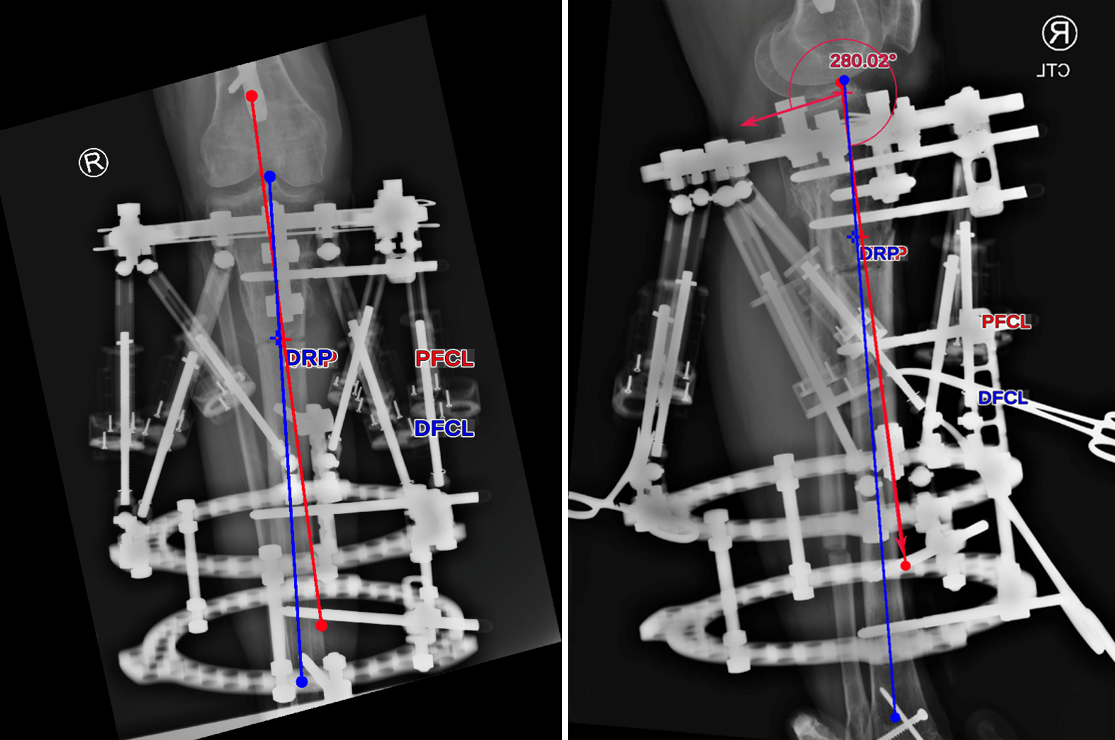

- 47-year-old woman s/p separate femur and tibia trauma

- Valgus knee with external rotation through femur

- Deformity analysis revealed that the angular deformity was coming from her proximal tibia.

The treatment plan was to remove the femoral intramedullary (IM) nail, to perform a derotational osteotomy of the femur with an internal saw, and then to refix the femur with a new antegrade IM nail.

The tibial deformity was planned to be managed with a MAXFRAME AUTOSTRUT™.